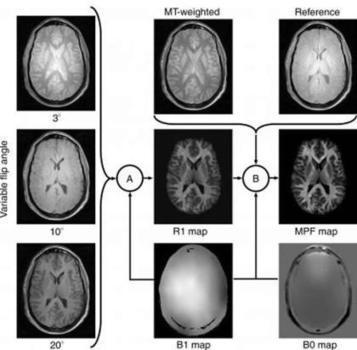

MRI Shows Gray Matter Myelin Loss Strongly Related to MS Disability

A new MRI study finds myelin loss in the gray matter of people's brains with MS is closely correlated with the severity of the disease.